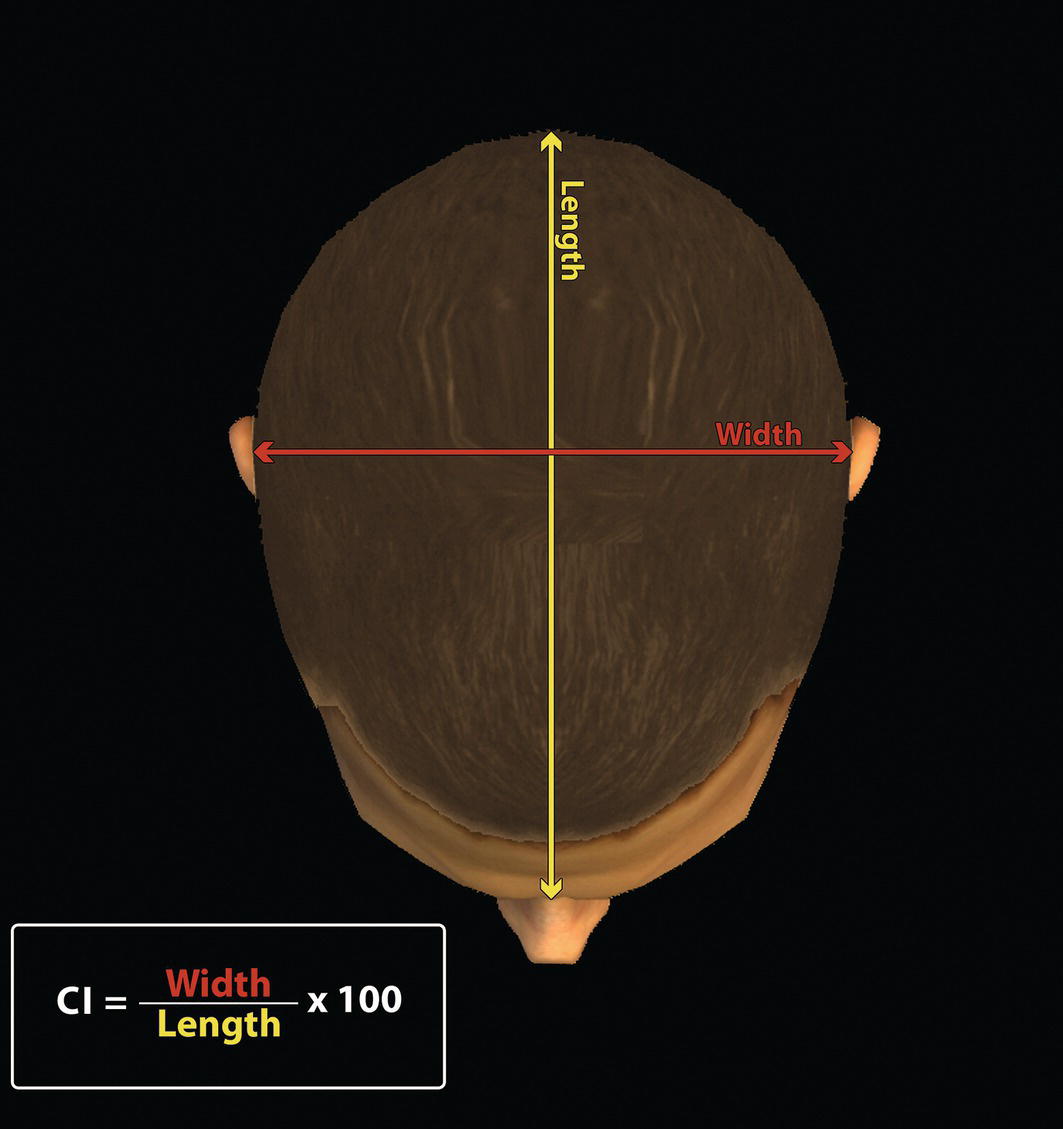

‘It is the common wonder of all men, how among so many millions of faces, there should be none alike’. Sir Thomas Browne (1605–82), English physician and writer, Religio Medici (1643)1 Individual variability is a fundamental principle in human biology. One of the most variable and distinguishable parts of the human body is the craniofacial complex. Clinicians will often compare a patient’s craniofacial measurements and proportions to the so‐called population norms (normative values) or even to classical ideals. However, Simon (1926) stated: ‘all we ever find are variations; an exact, ideal normal does not exist, cannot exist. And this is our enigma; in theory we will never find the normal, in practice we forever feel its need and apply it constantly’.2 The use of population norms may be logically enhanced by evaluating normal ranges of variability. Therefore, clinicians must have a thorough understanding of the normal ranges of variability in every aspect of craniofacial form, depending on age, sex and ethnic variability. Developmental disorders, as well as traumatic injuries and pathological conditions, may lead to deformities of the head and the face. Therefore, clinicians need to have a thorough understanding of the normal anatomy and morphological range of variation of the craniofacial complex in both males and females of different ages and ethnic groups, to act as guidelines when treatment planning the restoration of normal craniofacial proportions. Classifications that are useful for descriptive purposes include: A proportion index provides a numerical expression of the proportionality of a region of the craniofacial complex. The use of proportion indices dates back through the history of craniometry, particularly in the late nineteenth century. Linear (chord) or surface (arc) distances of the skull were measured between a variety of defined craniofacial landmarks; with any two measurements, the smaller was expressed as a percentage of the larger in order to provide a proportion index value. These could be used to provide an indication of skull shape. Figure 8.1 Determination of the normality or abnormality of any craniofacial measurement (or proportion index value) obtained from patients may be evaluated by comparison with the normative values obtained from a normal (average representative) population sample. The normal range of measurements is provided by the mean ±2 standard deviations (SD). The shape of the normal distribution curve shown is determined by the population standard deviation. Craniofacial parameters with small SDs have narrow, taller curves and those with large SDs have broader, flatter curves. Approximately 68% of all values fall within the range of ±1 SD from the mean and 95% within the range of ±2 SD from the mean. The normal range of variability for any craniofacial parameter is taken as being equal to the mean ±2 SDs. Greater differences may be perceived as deformities of gradually increasing severity. The leading researcher in the field of craniofacial anthropometry from the mid‐1960s to the early 2000s was Leslie Farkas, from the University of Toronto. Farkas et al. collected a large quantity of highly relevant anthropometric data between 1968 and 1984, from 2564 individuals.3 These data were used to provide 166 individual facial ratios, presented as proportion indices. In the creation of an index, the smaller measurement is multiplied by 100 (numerator) and divided by the larger measurement (denominator). Thus, a proportion index involves two linear craniofacial anthropometric measurements, with the smaller being expressed as a percentage of the larger. Proportion indices permit objective, quantitative assessment of facial morphology and proportions. Farkas3 identified two basic categories of proportion indices: Each proportion index will have a mean index value and a range of variation for a given population group, based on age, sex and ethnicity. The standard deviation (SD) determines the normal (average) range of variability of an index, from 2 SD below to 2 SD above the mean. Index values within this normal range are regarded as variations of normal proportions.4 Measurements within ±1 SD of the mean are regarded as optimal. The relationship between two measurements is disproportionate if the proportion index value is outside the normal range (Figure 8.1).4 For a number of facial parameters, single morphological measurements or proportion index values may have a large SD and, therefore, wide normal ranges of variation; as such, only measurements or proportion index values which differ considerably from the mean of the population will be perceived as deformities. Conversely, other facial parameters may have very small normal ranges of variability, in which case even a small difference from the mean may be perceived as a deformity. The cephalic index (index cephalicus) is a numerical expression of the ratio between the head width (biparietal diameter) and head length (fronto‐occipital diameter) of a living person. The cephalic index (CI) is calculated by the formula (Figure 8.2): Figure 8.2 Cephalic index. Where: The cephalic index is used in anthropometry to classify head types as (Table 8.1; Figure 8.3): Table 8.1 Classification of anatomical head types Index values according to Martin and Saller.5 Figure 8.3 Head types. The highest cephalic index values occur in the Chinese and the lowest values in African Americans. The larger index values of the Chinese differ significantly from those of whites or blacks (Table 8.2).6 A comparison of the cephalic index values of three ethnic groups was undertaken; North American Caucasians, northern European (German) and eastern European (Czech). The index values indicated a mesocephalic head type for both sexes of North American Caucasians and northern Europeans; and a brachycephalic (short‐wide) head type for the eastern Europeans.6 The head circumference is measured in the horizontal plane around the head, through the glabella and opisthocranion. However, it may be measured across ophyron (the point ‘On’, in the mid‐sagittal plane, of a line tangent to the upper limits of the eyebrows) rather than glabella in order to eliminate the effect of development of the frontal sinuses and superior orbital rims on head circumference.5,7 African Americans have the largest and the Chinese have the smallest head circumference for both sexes. The head circumference is slightly larger for blacks than for whites for both sexes.6 The initial step in facial analysis involves the examination of the face in frontal view in order to assess the overall facial shape. The variety of facial shapes is almost limitless. However, a simple assessment will allow an overall categorization of the basic facial shape. The basic facial shape in frontal view may be any combination of the following: Table 8.2 Cephalic index of three ethnic groups Data modified from Farkas.6 SD = standard deviation. Table 8.3 Head circumference of three ethnic groups Data modified from Farkas.6 SD, standard deviation. Figure 8.4 Facial height‐to‐width ratios. Variations in facial height and width result in an innumerable variety of the three basic facial shapes (round, square and triangular). For example, an oval facial type is a combination of an overall round face combined with increased vertical facial height and/or reduced facial width. The relationship of vertical facial height to facial width is an important indicator of overall facial shape. There are three methods of evaluating the vertical facial height‐to‐width proportion. These may be presented as proportions, percentages or indices: The facial index (index facialis or index of the morphological face height) is a numerical expression of the ratio between the facial height (nasion to menton) and the bizygomatic facial width (zygion to zygion) of a living person. The facial index (FI) is calculated by the formula: Where: The facial index is used in anthropometry to classify faces as (Table 8.4; Figure 8.6): Figure 8.5 Facial types according to Albrecht Dürer. (Modified from Dürer, 15288.) Figure 8.6 Facial types. Table 8.4 Classification of anatomical face types Index values: male according to Garson, 1885;9 and female according to Martin and Saller, 1957.5 The term facial divergence was introduced by the orthodontist‐anthropologist Milo Hellman,10 although the concept had been described by Albrecht Dürer (1528) (Figure 8.7).8 It is essentially a description of the slope or inclination of the face in the sagittal plane (Figure 8.8). It is determined by the sagittal position of soft tissue pogonion (Pog’) and subnasale (Sn) relative to a vertical line dropped from glabella (G’), with the subject’s head in natural head position. The factor that discriminates and distinguishes facial divergence from profile convexity or concavity is the sagittal position of subnasale (Sn) relative to the G’‐Pog’ line. In order for the face to diverge anteriorly or posteriorly, yet not to exhibit signs of convexity or concavity, subnasale (Sn) must be on or nearly on the G’‐Pog’ line; i.e. the upper facial plane (UFP, G′‐Sn) and the lower facial plane (LFP, Sn‐Pog’) are in a straight line, but diverge anteriorly or posteriorly. Figure 8.7 Facial divergence according to Albrecht Dürer. (Modified from Dürer, 15288.) Figure 8.8 Facial divergence. Anthropometric data from North American Caucasian males and females with untreated Class I dental occlusions describing normal facial divergence and ranges of variability has been provided.11 Mean values of facial divergence are negative, with the faces being slightly posteriorly divergent. Anterior divergence does not occur until two standard deviations from the mean. Facial divergence is essentially an ethnic variation in facial profile form. With a straight profile, i.e. no excessive profile convexity or concavity, anterior or posterior facial divergence is compatible with a normal maxillo‐mandibular and dental occlusal relationship. Figure 8.9 Facial profile contour according to Albrecht Dürer. (Modified from Dürer, 15288.) Figure 8.10 Facial profile contours. The contour of the facial profile may be described as convex, straight or concave. This concept was described by Albrecht Dürer (1528) (Figure 8.9).8 With the patient in NHP, the overall contour of the facial profile may be described by the relationship between two lines: the upper facial plane (UFP), connecting glabella (G’) to subnasale (Sn), and the lower facial plane (LFP), connecting subnasale to soft tissue pogonion (Pog’). In a straight profile, these two lines form a nearly straight line. Such a facial profile is termed orthognathic (Greek orthos: correct or straight; gnathos: jaw). An angle between these two lines indicates facial profile convexity (pogonion behind relative to subnasale in the sagittal plane), or facial profile concavity (pogonion ahead relative to subnasale in the sagittal plane). A convex profile indicates a skeletal Class II jaw relationship (and/or sagittal chin deficiency), and a concave profile indicates a skeletal Class III jaw relationship (and/or sagittal chin excess). However, profile convexity or concavity does not of itself indicate whether the maxilla or mandible/chin is at fault (Figure 8.10). Legan and Burstone12 described the angle of facial convexity for the soft tissue profile. It is formed by the two intersecting lines, the UFP (G′‐Sn) and the LFP (Sn‐Pog′). The mean value is estimated to be 12° ± 4°. An increase in the angle in a clockwise direction is positive; anticlockwise is negative. A high positive value suggests facial profile convexity and a Class II skeletal jaw relationship; a smaller positive value, or a negative value, suggests facial profile concavity and a Class III skeletal jaw relationship. However, the value of this angle does not reveal whether the maxilla or mandible/chin is responsible for the sagittal jaw discrepancy. Figure 8.11 Angle of facial profile convexity (facial contour angle). Downs13 described the angle of convexity, formed by the intersection of line nasion to point A (NA) and line point A to pogonion (A‐Pog). Superior extension of the A‐Pog line forms an angle with the NA line; if behind the NA line, the angle is read as positive, indicating a Class II (convex) skeletal profile. A negative angle of convexity indicates a Class III (concave) skeletal profile. Downs provided a range of values from −8.5° to 10°, with a mean of 0°. Again, as with the facial contour angle, the angle of convexity does not determine the localization of the deformity to the maxilla or mandible/chin. An investigation was carried out with the objective of assessing how lower facial profile convexity influences perceived attractiveness. The lower facial profile of an idealized image was altered incrementally between 14° and −16°, creating a range of images which were evaluated by pretreatment orthognathic surgery patients, laypeople and clinicians. A straight profile was perceived as most attractive and greater degrees of convexity or concavity deemed progressively less attractive, but a range of 10° to −12° was deemed acceptable; beyond these values surgical correction was desired. Patients were most critical, and clinicians were more critical than laypeople.14 The facial angle indicates the relative sagittal prominence of soft tissue pogonion. It is formed by the intersection of the true horizontal plane (or Frankfort Horizontal plane) with a facial vertical plane (N′‐Pog’). The angle should be approximately 90°–92°. A greater angle indicates prominence of soft tissue pogonion; an angle less than 90° indicates retrusion of soft tissue pogonion. The soft tissue facial angle does not of itself determine the aetiology of the sagittal position of soft tissue pogonion, which may be due to one or a combination of: Consequently, the facial angle must be used in conjunction with other measurements and analyses. In addition, when constructing the facial vertical line (N’‐Pog’), if the sagittal position of nasion is not acceptable, it may be adjusted to a more ideal position. The alternative is to use soft tissue glabella (G’) rather than nasion. Downs13 described the facial angle as the inferior inside angle in which the facial line (N‐Pog) intersects the Frankfort Horizontal plane. Downs found a mean value of 88° with a range of 82°–95°. It indicates the relative sagittal position of the mandible/chin to the upper face. Figure 8.12 Facial angle. FH, Frankfort Horizontal plane; TrH, true horizontal plane. Figure 8.13 The relationship of the cranial base angle (saddle angle) and anterior cranial base length on the jaw relationship. The relationship of the anterior to the posterior cranial base is of particular importance in the diagnosis of facial profile contour. This relationship depends on the extent of growth at the sphenoethmoidal and spheno‐occipital synchondroses. The cranial base angle (or saddle angle) represents the orientation of the anterior cranial base (SN line) relative to the posterior cranial base (S‐Ba line).15 The average adult values (bearing in mind that there is negligible change in this angle after the age of six years) for the angle N‐S‐Ba are16: As such, the cranial base angle is an important determinant of craniofacial form, as it influences the sagittal position of the face relative to the neurocranium and the sagittal prominence of the mandible relative to the maxilla. A significantly increased cranial base angle contributes to a skeletal Class II jaw relationship, whereas a reduced cranial base angle contributes to a skeletal Class III jaw relationship. If basion is difficult to identify on a lateral cephalometric radiograph, articulare may be used instead, i.e. the posterior cranial base is drawn between sella and articulare. The average adult values for the angle N‐S‐Ar are16: The anterior cranial base length, measured from sella to nasion, may also influence the jaw relationship. For example, increased anterior cranial base length may lead to a Class II jaw relationship, with the maxilla ahead of the mandible in the sagittal plane, whereas reduced cranial base length may lead to a Class III jaw relationship, with the maxilla behind the mandible in the sagittal plane. The average adult values for the anterior cranial base length are16: Figure 8.14 Parasagittal profile contour. An additional and extremely important consideration is the description of the parasagittal profile (Figure 8.14). It is necessary to evaluate the sagittal relationships of the soft tissues from the infraorbital area to the paranasal area to the parasymphyseal area. For example, maxillary hypoplasia may lead to lack of bony support and flattening in the infraorbital region and paranasal hollowing; with a normal parasymphyseal area, this will lead to the appearance of a concave parasagittal profile. The directional pattern of facial growth has a significant effect on facial profile form. Deviations from the normal pattern of jaw growth may be in a predominantly vertical or horizontal direction. Alternative terms are hyperdivergent facial growth pattern (referring to the excessive divergence of the maxillary, occlusal and mandibular planes in relation to each other and to the anterior cranial base).17 Such a pattern of growth leads to a hyperdivergent facial type, alternatively termed a high angle patient (referring to the increased mandibular plane angle), long face deformity or long face syndrome.18 If the hyperdivergent growth is the primary aetiology to an anterior open bite, the terms skeletal open bite or apertognathia (Latin apertus: open; Greek gnathos: jaw) may be used.19,20 The maxilla rotates downward and backward (posterior vertical maxillary excess), as does the mandible during growth. This leads to reduced sagittal projection of the chin. Such a vertical facial growth pattern will tend to be associated with a posterior pattern of mandibular growth rotation. Figure 8.15 Hyperdivergent, ‘high angle’ facial type.